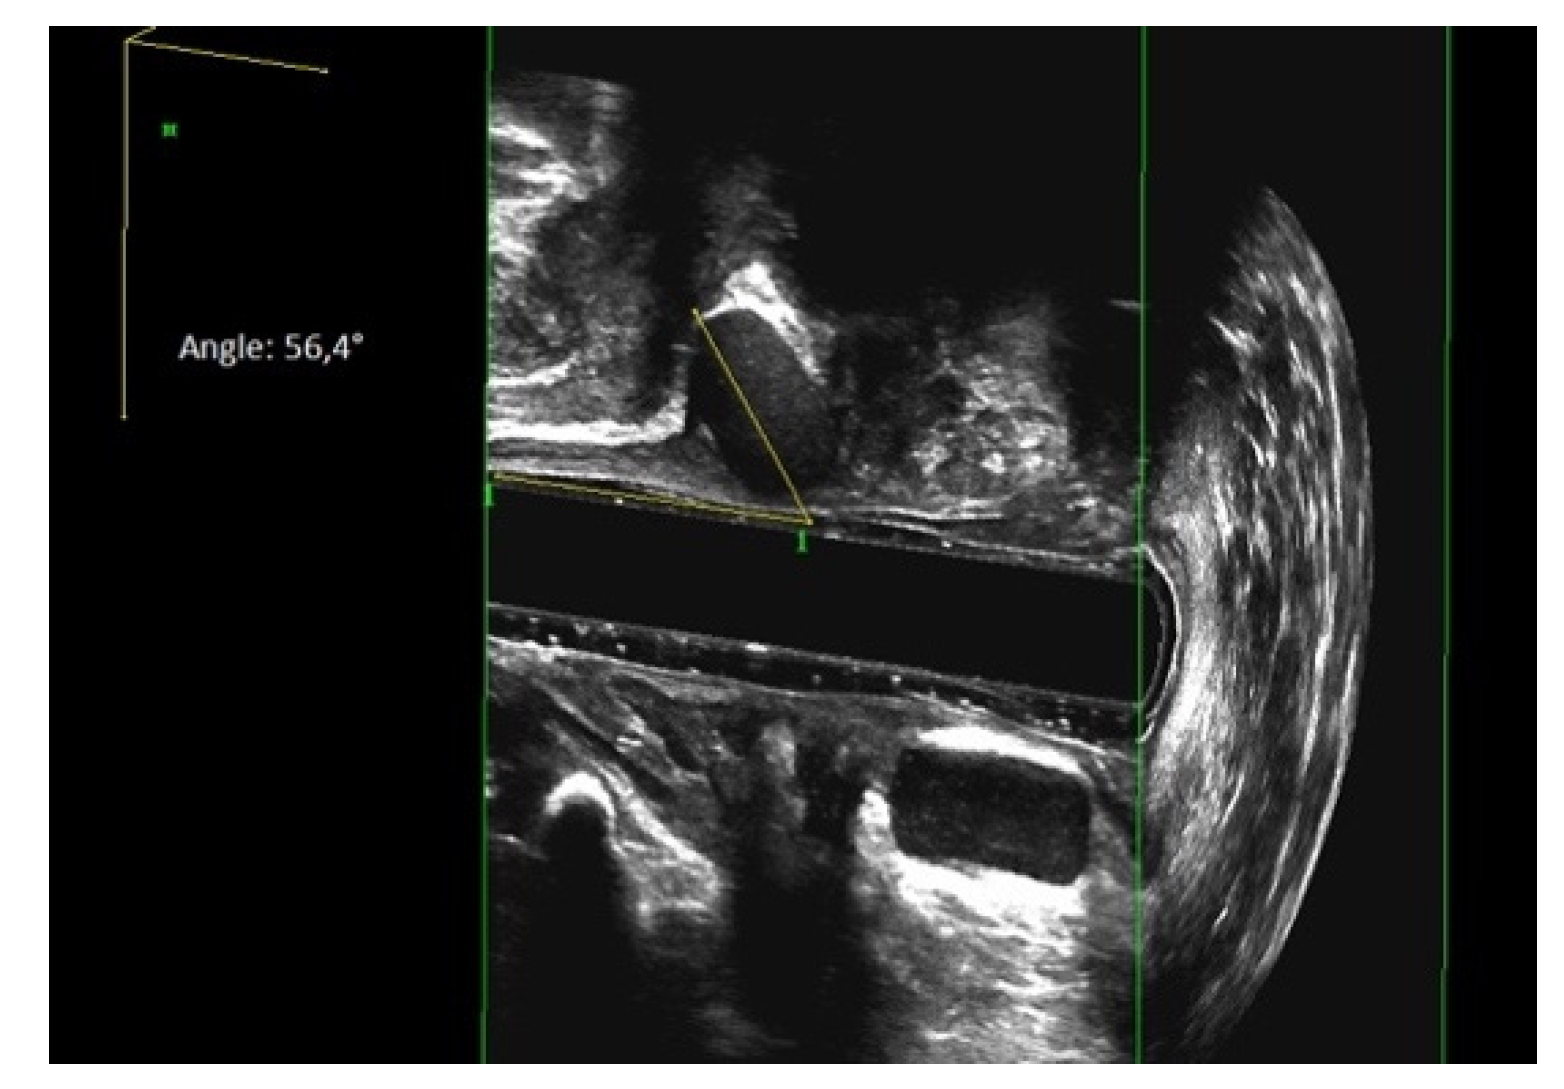

3.4. Evaluation of Sphinkeeper Implants

| EAUS—internal sphincter defect [grade], median (range) | 67.5 (38–121) |